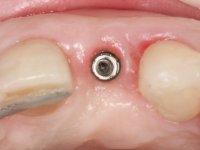

• Placement of an implant at the tooth site 2.2. Rehabilitation of the implant with a coronary and gingival component abutment. in which the screw access hole was "camouflaged" with a feldspathic veneer.

Treatment began with re-preparation of the cast post and core, with the purpose of placing the cervical finishing lines with an intra-sulcular location and simultaneously making a suitable temporary crown. With a very simple orthodontic treatment, the diastema was closed between the upper central incisors, and this position was stabilized with a wire placed on the palatal surface of the central, functioning as containment. Later, a slow orthodontic traction of tooth 2.2 was attempted, in order to reduce, although very slightly, the vertical bone loss in this area. At the end of the traction, tooth 2.2 was extracted and the area was provisionally rehabilitated with a composite resin crown bonded to the adjacent teeth. A dental implant was placed in the area of tooth 2.2 and the temporary crown was again bonded to resin, provisionally rehabilitating the patient during osseointegration. In tooth 1.3 a gingivectomy with an electric scalpel was performed, with the intention of raising the cervical level of 1.3 achieving greater harmony with tooth 2.3. Stabilized soft tissues were impressed using the open tray technique with putty and light addition silicones. Collection of the color of both the dental component and soft tissues was done by the ceramist in the office. In the laboratory, the impressions were transferred to plaster and gave origin to work models that were properly analyzed. It was decided to assemble a metal-ceramic abutment screwed onto the implant. This abutment was cast with a noble alloy and subsequently coated with coronary and gingival ceramics. Due to the inclination of the implant, the screwing inevitably conditioned the exit of the screw hole through the vestibular surface. In order to conceal this situation, the design of the abutment has already been conceived with the intention of accommodating on the vestibular surface the bonding of a feldspathic veneer. This abutment was tested in the mouth and adjustments were made in the gingival ceramic component. Its adaptation to the soft tissues was done in a subtractive way, with a drill, as well as additive, adding resin composed of gingival tonality.

This addition of resin would guide the ceramist in the final placement of the gingival tonality ceramic. The crown that would rehabilitate tooth 1.3 was cemented in this test session with glass ionomer cement, reinforced with composite resin. Once the laboratory work was finished on the veneer for tooth 1.2, the abutment, and the veneer for the implant, this was bonded in the mouth, after placement of the absolute insulation. The work completely satisfied the patient. For eight years, the patient had periodical check-ups, and was pleased with the treatment, but also began to show interest in an aesthetical intervention on the upper central incisors. Once the second phase of our intervention was decided, dental preparation of teeth 1.1 and 2.1 was performed for the placement of two feldspathic veneers. Particular care was taken in the distal inter-proximal preparation adjacent to the abutment of the implant.